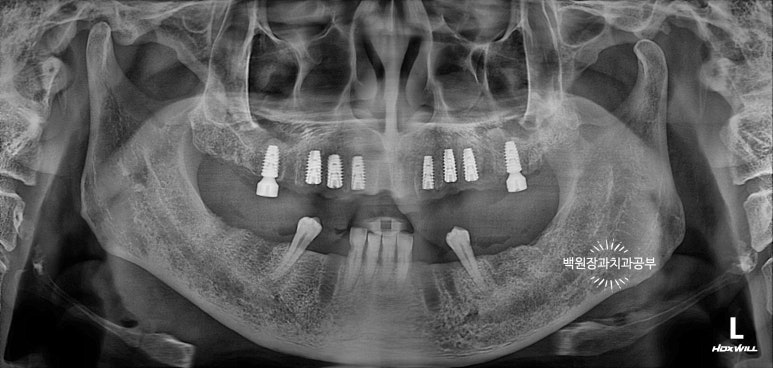

위턱뼈 임플란트 1차수술부터 시행하였습니다.

위턱 임플란트 1차수술 후

위턱 임플란트부터 심어보았습니다. 그 이유는 위턱뼈와 아래턱뼈의 질의 차이 때문입니다.

좌우측 첫번째 대구치 부위의 임플란트는 상악동 뼈이식술도 함께 시행하였습니다.

사실 치과 파노라마만 보시기에 '임플란트가 생겼네!' 정도로 인지 하시겠지만,

생각보다 많은 공이 들어가는 치료입니다..!!! 여러 앞니 임플란트들도 많고 어려운 뼈이식을 시행했어요.!!

약 1달 뒤 아래턱뼈 남은 치아의 발치와 함께 임플란트 1차 수술을 시행하였습니다.

아래턱 임플란트 1차수술 후